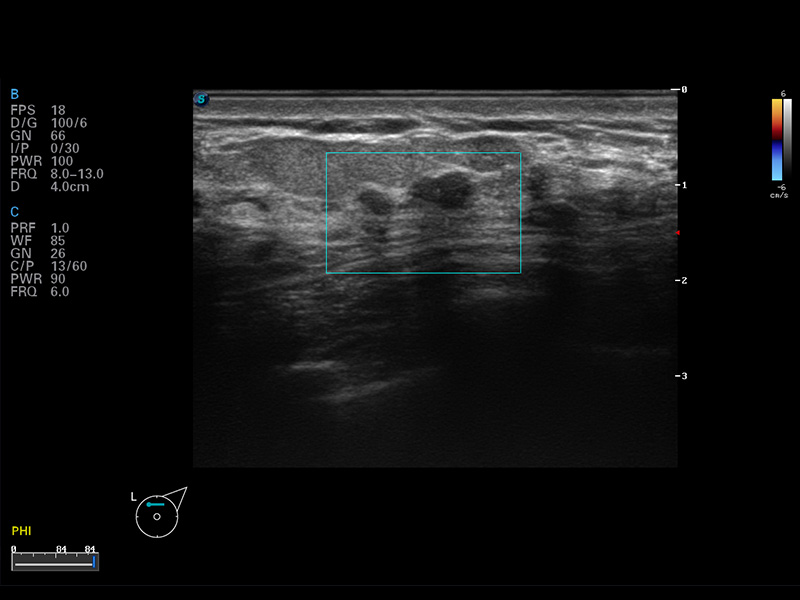

S8 EXP便携式彩色多普勒超声诊断仪是美狮贵宾会官网研发的高端全身应用型便携彩超。高通道的VIS平台融合可视化(Visual)、智能化(Intelligent)和人性化(Smart)的特点,配以美狮贵宾会官网自主研发生产的探头大家族,使您能够快速、准确的获得病人信息,提高工作效率的同时减轻疲劳。

成像技术

多波束形成器

μ-Scan微米成像

谐波成像

实时宽景成像

空间复合成像

3D/4D成像